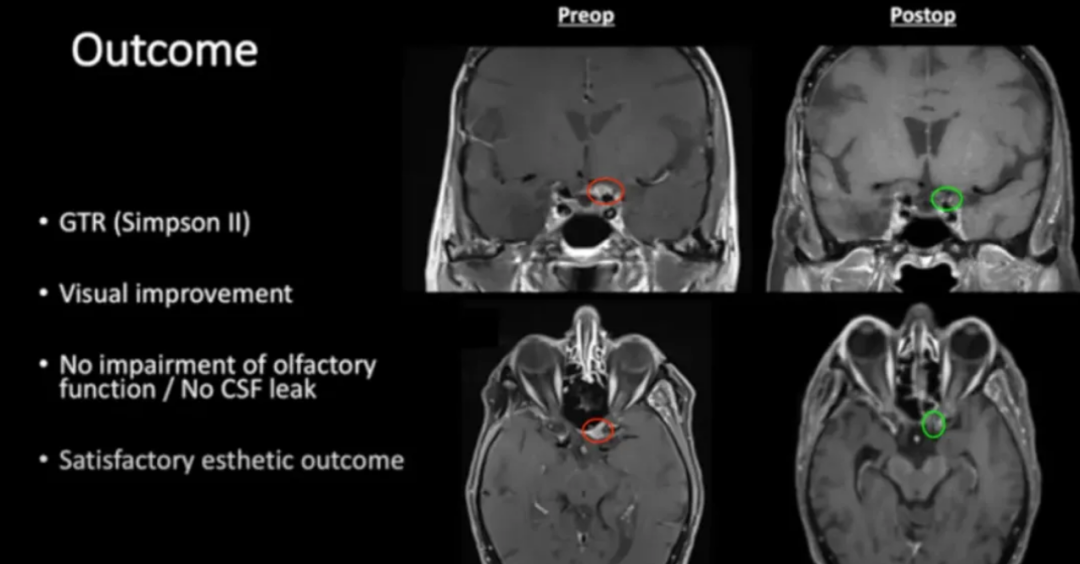

2005年,75岁女性患者行右侧海绵窦脑膜瘤切除术。11年后左眼视力持续下降,检查发现新脑膜瘤压迫视神经管下侧。

86岁高龄患者选择手术治疗。Froelich教授采用内镜辅助右额下入路肿瘤全切术,实现辛普森II级切除。术后视觉功能显著改善,嗅觉功能保留完整,无脑脊液漏发生。

术前及术后MRI对比显示肿瘤完全切除。